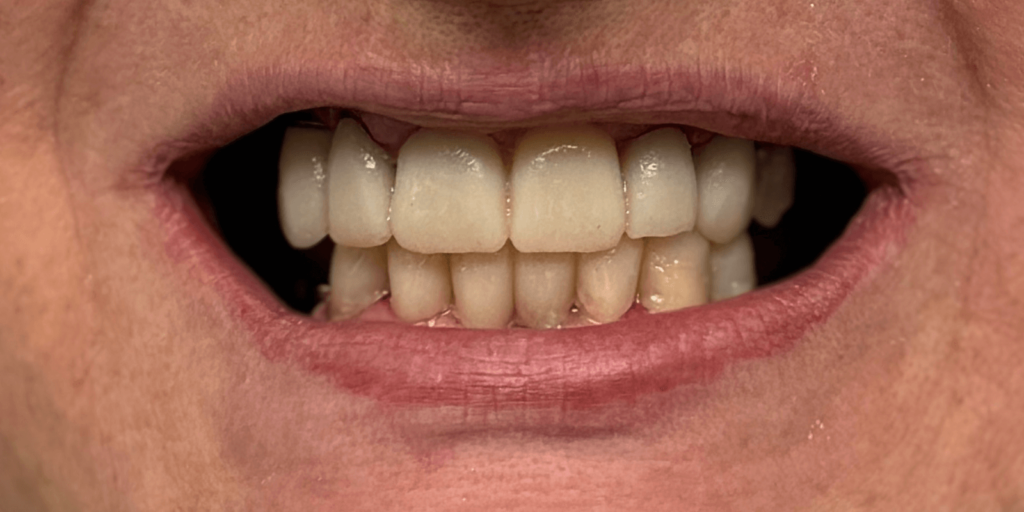

Итог

С момента первого визита прошло чуть менее трех месяцев. И когда пациентка в последний раз посмотрела в зеркало – мы увидели не просто улыбку. Мы увидели, как человек словно вернулся к себе.

Ее глаза засияли. Плечи расправились. Она начала смеяться громче. Ее жизнь изменилась не потому, что появились новые зубы, а потому, что исчезли все комплексы, которые годами мешали жить свободно.